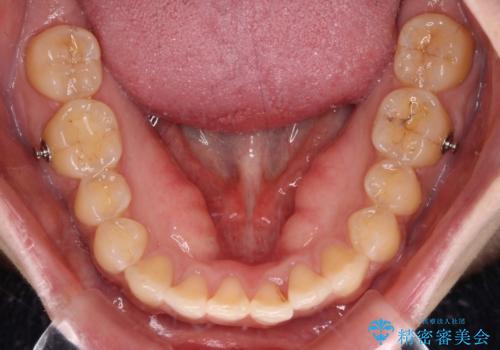

舌のトレーニングをしっかりと行っていただき、上下前歯をしっかりと接触させることができました。

咬合力が強いため、治療途中に奥歯が咬み合わない期間が続きましたが、上下の奥歯でゴムかけを行っていただき、違和感なく咬み合うように仕上げることができました。